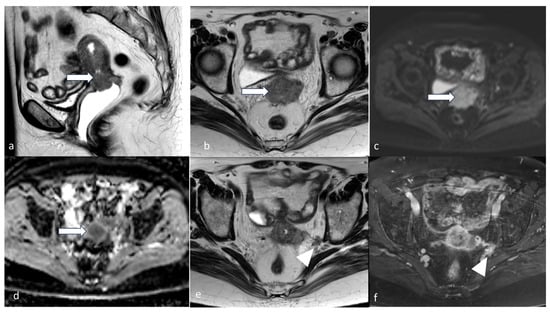

5.3. Magnetic Resonance Imaging (MRI)